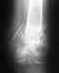

Добрый день.39 лет, мужчина, правая стопа.Травма получена при ремонте машины которая скатилась с эстакады захватив и протащив меня с собой метров 20.Не могу вспомнить попала нога под колесо или просто зацепилась за что то.В травме сделали снимок, сказали что есть подозрение на перелом таранной кости, направили в больницу.В больнице сделали снимок, сказали что видно плохо, но вроде перелом, ложитесь на операцию, а там видно будет...КТ сделано на 2й день, после травмы.Гипс наложен, нога не болит, отечность легкая.Прошу проконсультировать на предмет необходимости хирургического вмешательства, и вобще дальнейших действиях.Спасибо

• Кликните для загрузки файла 2 001.jpg

Надо делать КТ. По единичной плохо сфотографированной рентгенограмме ничего определенного не предложить.